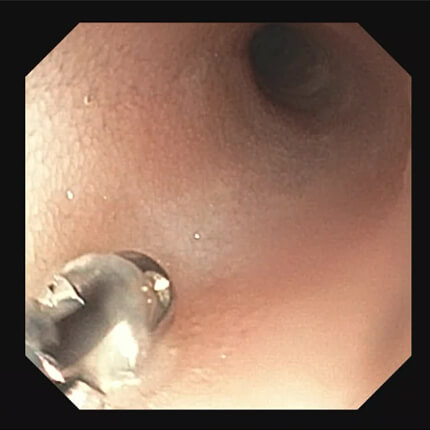

【胃角部】